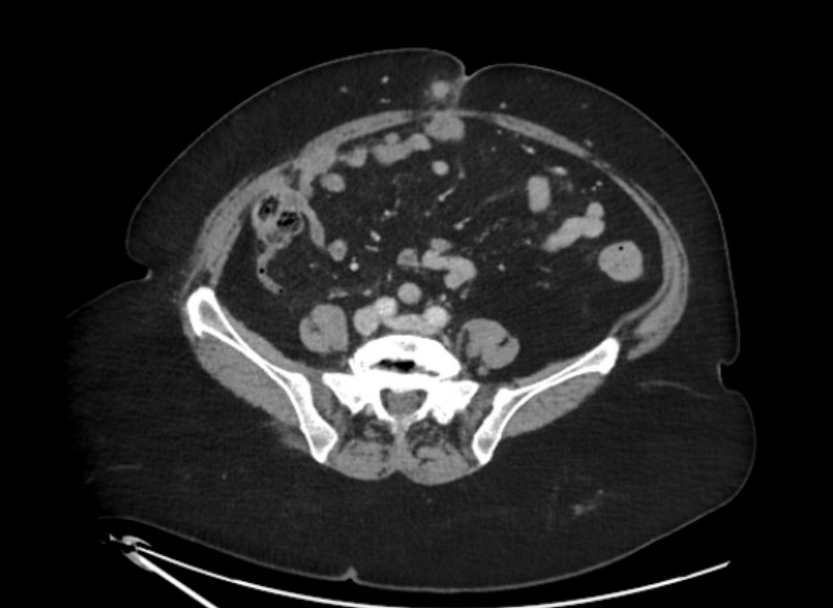

Ecografía reglada de partes blandas: Nódulos subcutáneos e intrabdominales sospechosos de malignidad. La tomografía abdominal describe múltiples implantes sólidos peritoneales y en pared abdominal, compatibles con metástasis.

Nódulo de Hermana María José, correspondiente a metástasis umbilicales de carcinoma de endometrio, con carcinomatosis peritoneal. Diagnóstico diferencial con lipoma, quiste sebáceo, fibroma.

El Comité multidisciplinar de tumores decide Biopsia guiada por ecografía + PET/TC que confirma múltiples implantes hipermetabólicos. Biopsia: Carcinoma de endometrio con pérdida de expresión de PMS2 y MLH1, confirmando la naturaleza metastásica del nódulo umbilical. Tratamiento con citoreducción e Inmunoterapia.